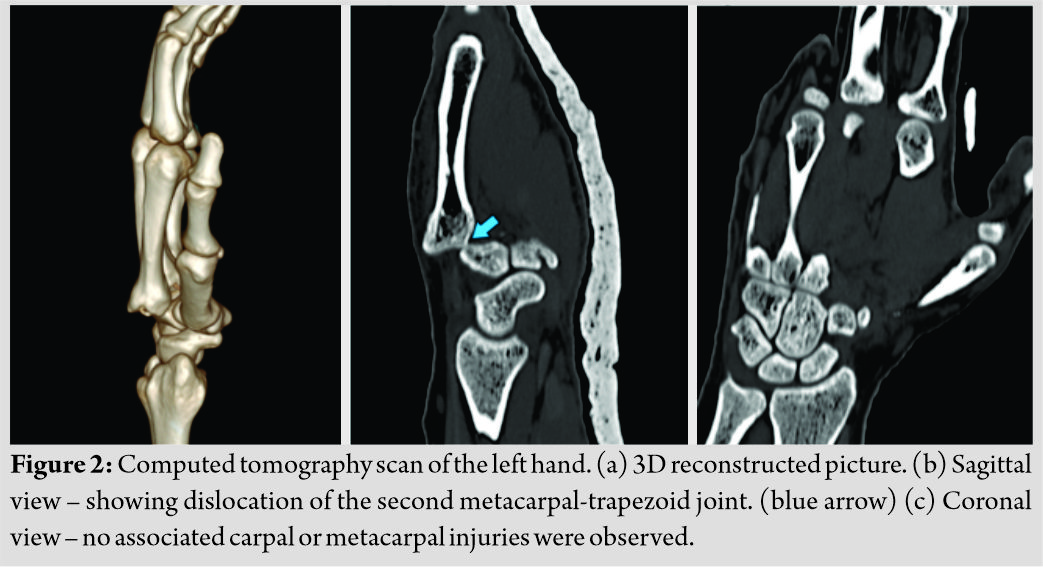

The computed tomography (CT) scan of the left wrist revealed the same, and no associated carpal injuries were observed (Fig. 2a-c). Under general anesthesia, a closed manipulation was attempted in the form of exaggerating the deformity and maneuvering a gentle distally directed force over the dislocated second metacarpal base which reduced with clunk and resolution of the deformities (Fig. 3a). The concentric reduction was attained and the articulation stabilized with a 1.5 mm Kirschner wire (K-wire) passed percutaneously under fluoroscopy guidance (Fig. 3b-d).